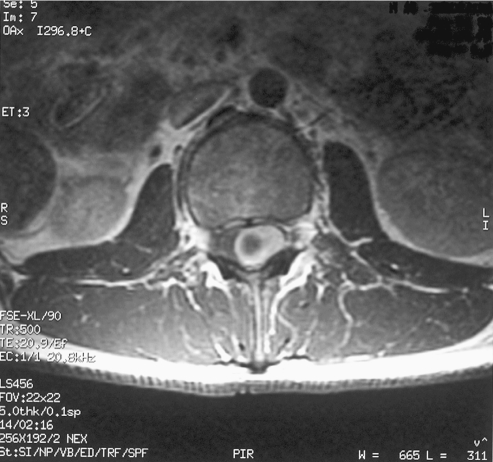

Fig. 2.

Thoracic Intradural lesion (case 1)